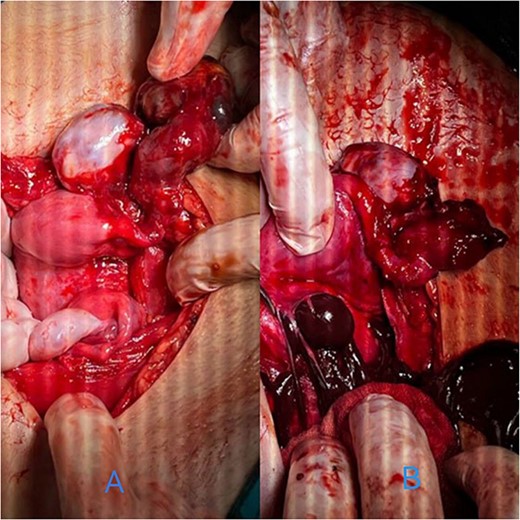

By surgically opening and reaching the abdominal cavity, two uteruses were found, along with a mass filling the pelvic cavity, measuring about (8 × 7 cm). We also saw a didelphys uterus with normal right and left ovaries, a hematoma filling the left fallopian tube, and an accumulation of blood within the vagina (hematocolpos) (Fig. 3).

(A) A hematoma in the left fallopian tube. (B) An accumulation of blood in the vagina.

The hematomas were drained (Fig. 4), and upon investigation, two cervixes were found: one for each uterus and a single vagina with a closed end, representing a transverse vaginal diaphragm.

The didelphys uterus after the left fallopian tube and vaginal hematomas were drained.